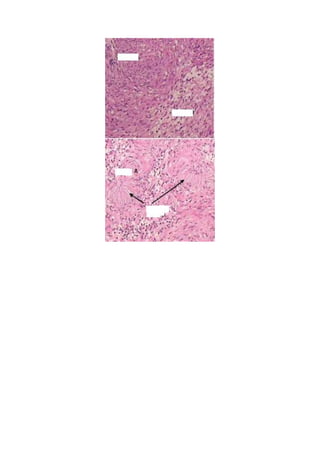

Este documento describe los diferentes tipos de vértigo, incluyendo causas centrales y periféricas, y explica cómo la duración puede indicar la etiología. Luego se enfoca en el schwannoma acústico, un tumor benigno del nervio vestibulococlear que representa el 8-10% de los tumores intracraneales en adultos y se origina en la porción vestibular del nervio. Los síntomas incluyen deterioro auditivo, tinnitus, pérdida de equilibrio, entumecimiento facial y debilidad muscular parcial.